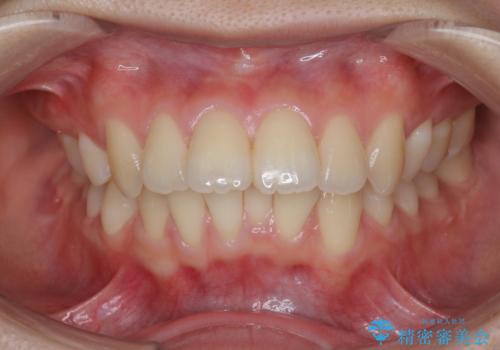

50代女性 八重歯を矯正治療 歯並びの中等度のがたつき